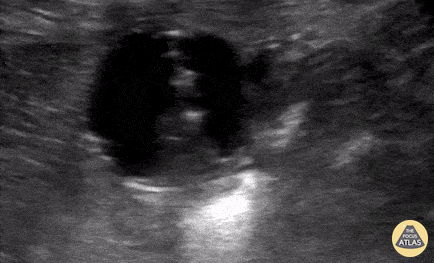

Pediatric gastrostomy replacement NOT in gastric lumen - not only do you not see the stomach wall between the gastrostomy bulb and abdominal wall, with injection of oral rehydration solution you see it outline the spleen tip (near end of clip). Cailin Frank